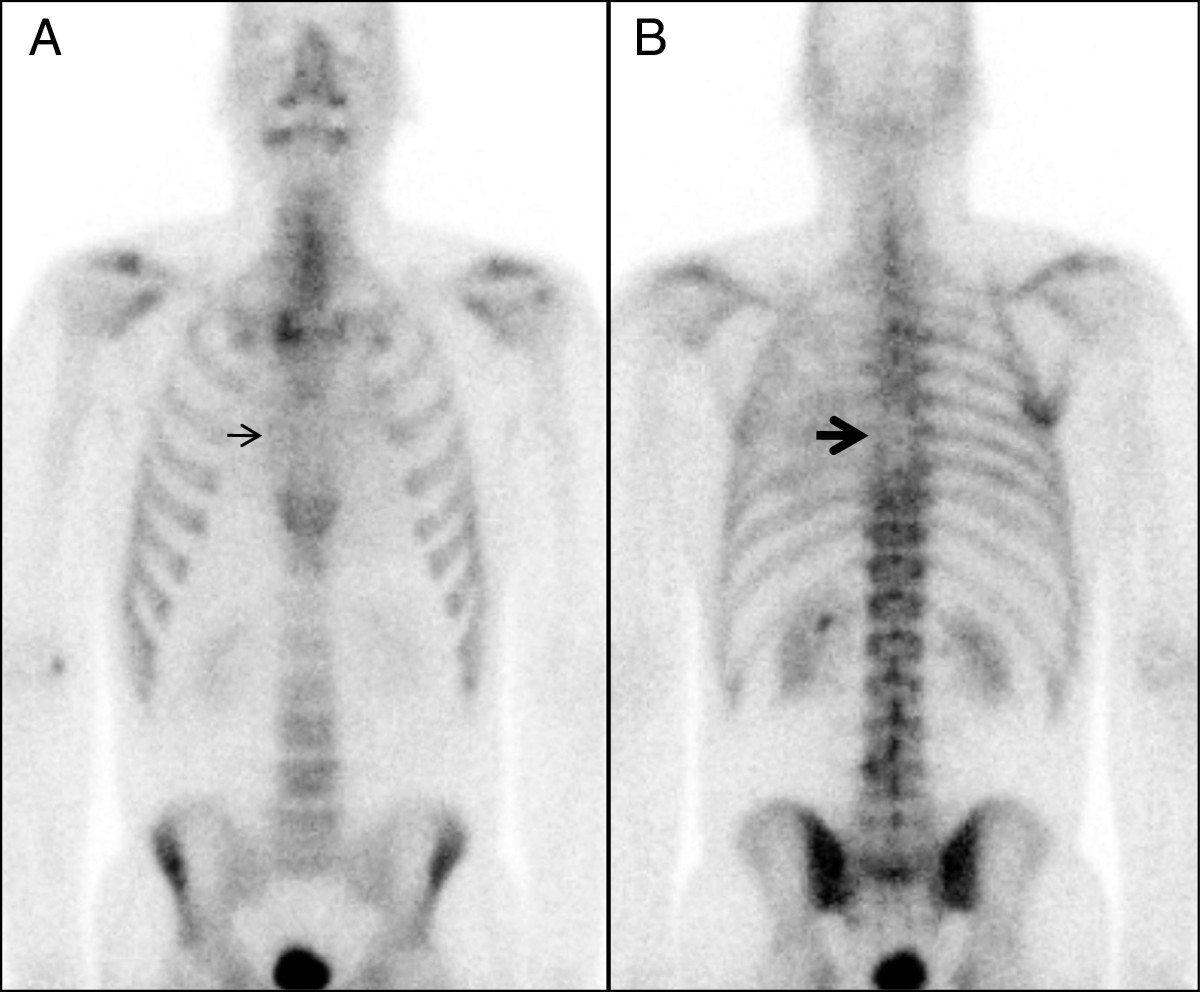

Figure 1 from Radiation Recall Reaction Two Case Studies Illustrating What Is Radiation Recall radiation dermatitis is one of the most common side effects of radiotherapy for cancer, affecting over 90. what is radiation dermatitis? It is also called radiodermatitis, x. Radiation dermatitis is a side effect of external beam ionizing radiation. radiation recall reaction is an uncommon and unpredictable. radiation recall is an acute inflammatory reaction confined to. . What Is Radiation Recall.

From www.semanticscholar.org